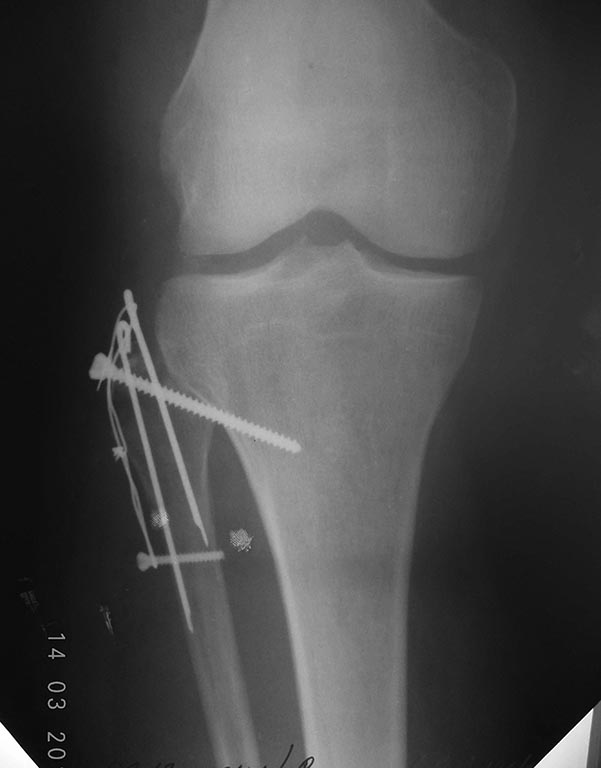

Вот результат. Явления неврит всё таки имеются.

Вторая проекция.